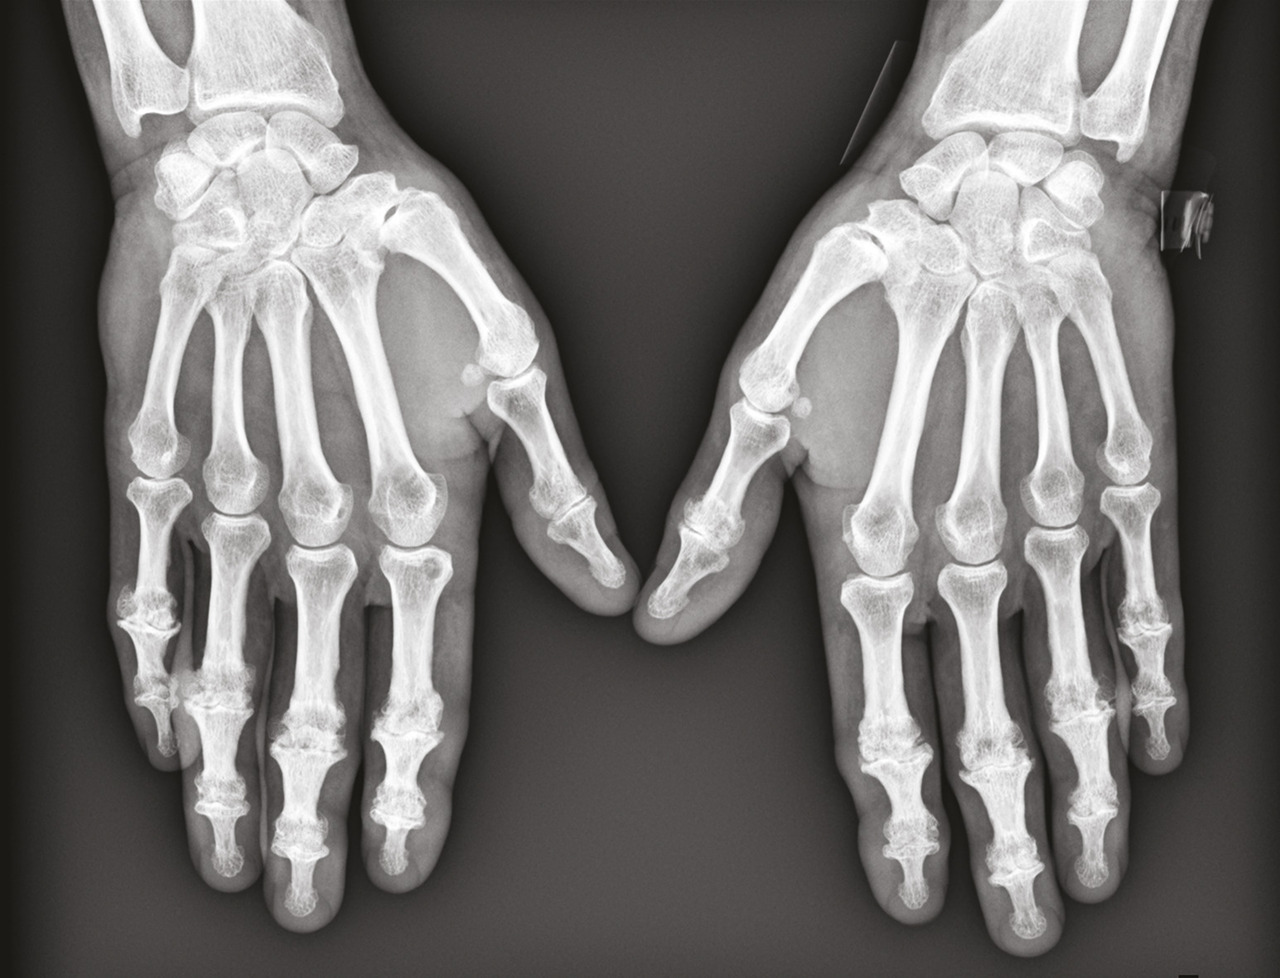

L’arthrose des doigts longs évolue souvent par crises douloureuses et peut se distinguer par des signes inflammatoires locaux, en regard des articulations concernées, notamment dans sa forme érosive (figures). Des nodosités peuvent être palpées : elles correspondent à l’ostéophytose du pourtour de l’articulation arthrosique. Une évolution vers l’ankylose des articulations distales est possible, à l’origine d’une déformation en position vicieuse et/ou d’un défaut de flexion, qui gênent considérablement la préhension.